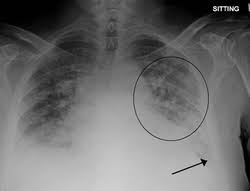

Pulmonary edema is a condition characterized by abnormal accumulation of fluid in the lung interstitium and alveolar spaces, leading to impaired gas exchange and respiratory insufficiency.

- Dyspnea, orthopnea

- Cough with pink frothy sputum

- Cyanosis

- Crackles on auscultation